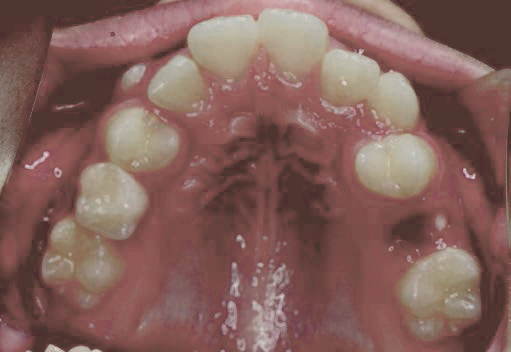

出っ歯

あごや骨格を正しく成長させる矯正治療

Aさん (矯正開始時:8歳)

Before

After

鼻がつまりやすく、口呼吸をしているために上あごが狭い状態でした。また上の前歯がかなり前へ傾いているため、お口をきちんと閉じていることができません。さらに、下の前歯もでこぼこしていました。

治療を終えて

装置によって上あごを拡大し、下あごを少し前へ成長させたことで、永久歯がきれいに並ぶスペースを確保しました。また、お口の機能が向上したことから鼻がよく通るようになり、口呼吸も改善され口も閉じやすくなったので顔の表情もよくなりました。

主訴・治療内容 下あごが後ろに下がり、出っ歯のようになっていることを心配して、無料相談に来院されました。

治療期間 2年半

費用 462,000円(税込)